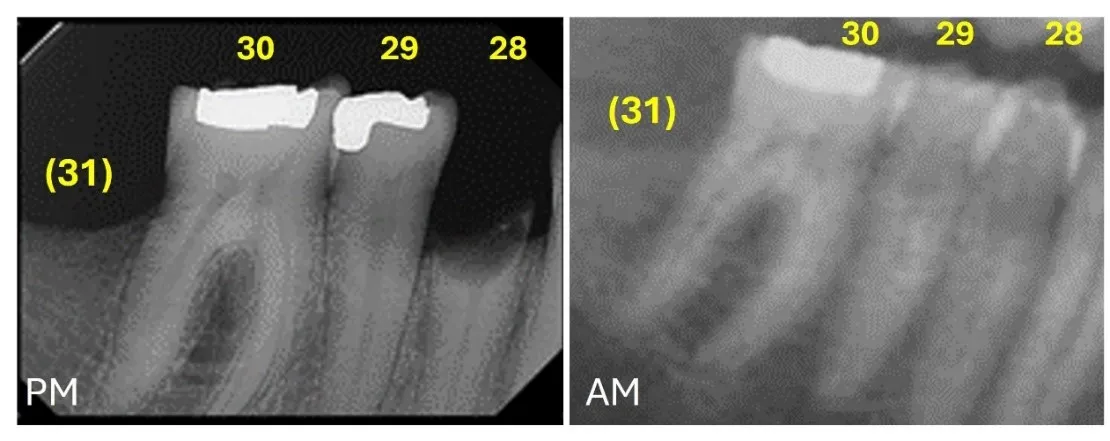

As previously mentioned in this article, the postmortem vs. the antemortem data comparison implies the evaluation of the consistencies and inconsistencies found in the data sets. This comparison is highly affected by the quality and completeness of the antemortem records, as well as the condition of the remains. The postmortem and antemortem odontograms and radiographs should be compared tooth-by-tooth [7], evaluating all the similarities and inconsistencies, and assessing whether these inconsistencies are reconcilable or irreconcilable. The principles of postmortem vs. antemortem odontological comparison are based on the differences in the dental and maxillofacial structures due to human variation, development and pathology, and the alteration caused by dental treatment, which can be visually and radiographically observed [6,7,12]. As such, the individual’s dentition changes throughout life. However, the changes are unidirectional [13], meaning that there are no reversals; this progressive change is fundamental to consider forensic odontology a reliable means of human identification. A match consists of several concordances between the postmortem and antemortem records. A restoration present in both data sets located in the same tooth, covering the same surfaces, and of the same restorative material represents a match (Figure 1). A reconcilable inconsistency consists of a discrepancy between the postmortem and antemortem records that may be explained by dental development or postformation changes, orodental disease and dental loss, new dental treatment or extension of a preexisting one, and skeletal trauma or surgery (Figure 2). Essentially, a reconcilable inconsistency will include all changes in the dentition that are plausible to have happened between the date in which the antemortem radiograph (or other record) was taken and the date in which the remains were found [5,6,8]. Reconcilable inconsistencies do not exclude the postmortem and antemortem records from corresponding to the same individual. An irreconcilable inconsistency includes any discrepancy between the postmortem and antemortem records that is not possible to occur (Figure 3). Tooth development and postformation changes are unidirectional, so the postmortem data cannot show an earlier stage of development for the same individual; a tooth presenting caries or a restoration cannot appear as healthy and not restored in the postmortem. Only one irreconcilable discrepancy is enough to exclude the antemortem and postmortem datasets from corresponding to the same individual.

Figure 2. Postmortem radiograph (PM) where #29 shows a disto-occlusal amalgam restoration and #28 shows only a root fragment present. Antemortem (AM) radiograph where #29 and 28 appear present and not restored (both reconcilable inconsistencies (Universal Dental Numbering System).